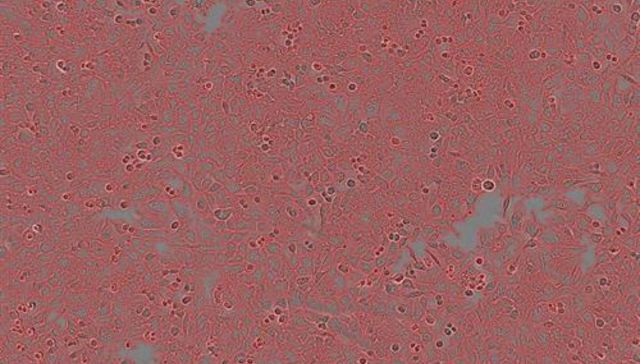

Bien, pero no tan bien

Las contagios a la baja en Italia, pero los fallecidos suben hasta los 192